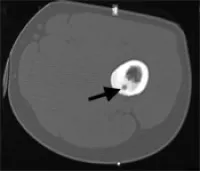

Imaging usually is very typical: X-rays show new bone formation and sometimes a small lucent spot (smaller than 1.5 cm), which is defined as the nidus. Computed tomography (cat scan, CT) is even better suited to show the new bone formation and the nidus. Because there may be a lot of inflammatory swelling and edema in the bone and soft tissues around the tumor magnetic resonance imaging (MRI) may sometimes be difficult to interpret and CT may be required to further assess these tumors. Radionuclide or bone scans show increased uptake of the radioactive tracer, this may sometimes be very focal.

CT scan of an osteoid osteoma of the thigh (femur), a small, round lytic focus (arrow) surrounded by dense bone is demonstrated.